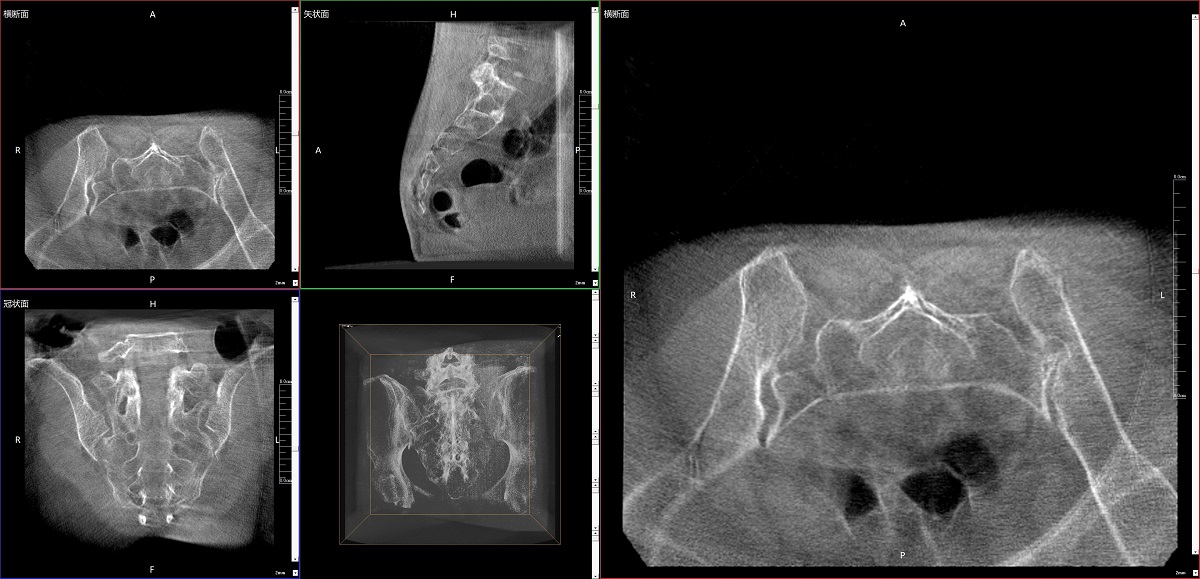

在骨科手術(shù)中,影像相當(dāng)于醫(yī)生的“眼睛”,要先“看得清",才能“算得準(zhǔn)” “打得穩(wěn)”。普愛醫(yī)療第三代平板三維C形臂協(xié)同醫(yī)院創(chuàng)傷導(dǎo)航機(jī)器人已開展多例“骨盆骨折微創(chuàng)手術(shù)”,成為上海市第七人民醫(yī)院手術(shù)技術(shù)創(chuàng)新的一大亮點(diǎn)。

普愛醫(yī)療第三代平板三維C形臂出色的二維透視和術(shù)中三維成像效果,為機(jī)器人提供了精確的術(shù)中影像依據(jù),協(xié)同提升手術(shù)整體的精準(zhǔn)度和效率,為患者帶來(lái)了更安全、更高效的醫(yī)療服務(wù)體驗(yàn)。